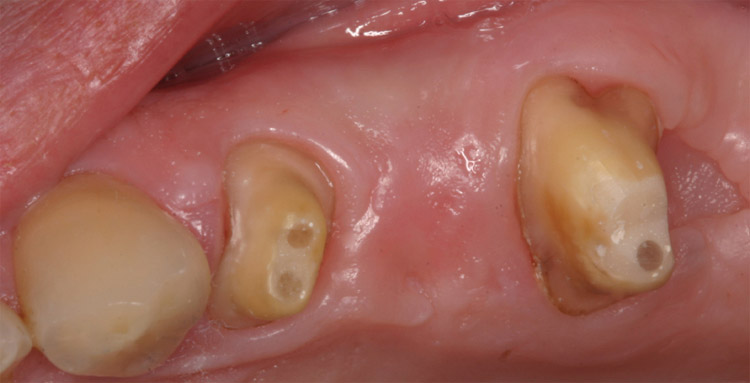

PONTE IN CERAMICA INTEGRALE

Ponte in ceramica integrale su

monconi devitalizzati di 2.4 e 2.6 con

edentulia del 2.5. Distalmente al 2.6 si

rinviene un sito post-estrattivo in fase di

guarigione.

partnership: Dott. S. Scolavino (2009)